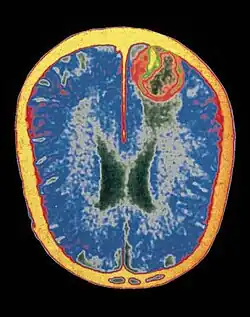

Estudos da esquizofrenia com imagens obtidas com o PET Scan[9] revelam uma relação entre uma menor ativação dos lobos frontais (vermelho) e aumento anormal da dopamina no c. striatum (verde)

9. Meyer-Lindenberg A; Miletich RS, Kohn PD, Esposito G, Carson RE, Quarantelli M, Weinberger DR, Berman KF (2002). "Reduced prefrontal activity predicts exaggerated striatal dopaminergic function in schizophrenia". Nature Neuroscience 5: 267–71.